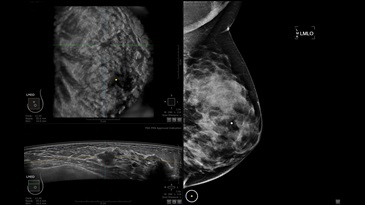

GE INVENIA ABUS – это современный УЗИ аппарат, который создан для точной и эффективной диагностики сканирования с высокой плотностью молочных желез. Выявляемость патологий раковых и предраковых стадий заболевания составляет 55%, что в конечном счете позволяет ставить врачу точные и своевременные диагнозы. Традиционные методы использования маммографии не показывают такой выявляемости, ограничиваясь лишь 3-38%.

УЗИ-аппарат GE INVENIA ABUS позволяет проводить максимально операторонезависимые процедуры, что значительно снижает риск неправильной постановки диагноза и сопутствующие издержки на обработку информации. Система готовит отчет в течение 3-х минут после сканирования, это безусловное преимущество по сравнению с обычным УЗИ сканером.

• датчик с изогнутой апертурой для качественного исследования

• сканирование одной грудной железы в трех проекциях не более 60 сек.;

• обработка результатов за три минуты.

Данное устройство классифицируется, как стационарное, используемое в многопрофильных клиниках, женских консультациях, медицинских центрах. Вес без учета дополнительного оборудования составляет 105 кг. Удобная колесная база позволяет оперативно маневрировать в ограниченных пространствах, в том числе передвигать устройство в коридорах клиники. Большой 17-ти дюймовый монитор с широкими углами обзора выводит максимально качественную картинку в формате Full HD.

Возможности встроенной УЗ-системы:

• Увеличение или уменьшение степени сжатия грудной железы;

• Функция автоматического сканирования активируется одним нажатием;

• Возможность отмены сканирования;

• Глубина проникновения УЗ-лучей – до 50 мм;

• Одно детализированное изображение можно получить менее чем за 1 минуту

• Многорядная светодиодная подсветка;

• Встроенный сверхширокий вогнутый датчик С15-6ХW.